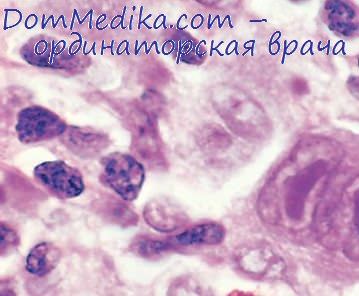

Микропрепараты: Лимфогранулематоз и Нодулярный Склероз